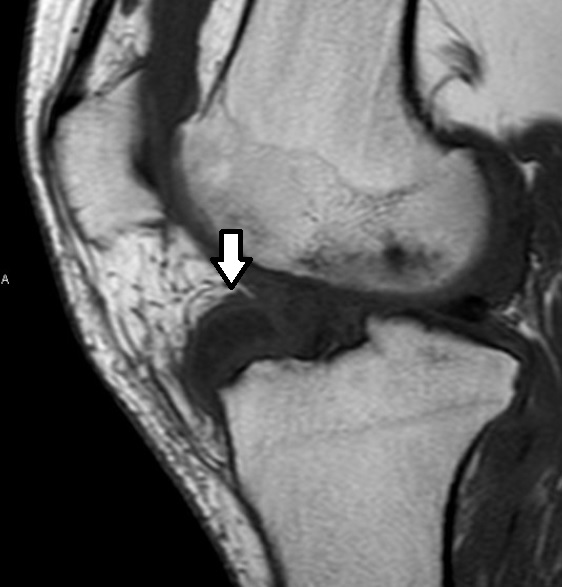

Abundante líquido intraarticular en espacio suprarrotuliano. Se extraen 50 cc de líquido seroso y se infiltra Scandinibsa y Celestone. En espacio infrarrotuliano en grasa de Hoffa se observa una masa bien delimitada de 2,23 x 1,73 x 1,65 cm, encapsulada y homogénea, con alguna línea hiperecoica horizontal (imagen 1).

En RMN plantean tumor de células gigantes versus artropatía gotosa tofácea (imagen 2).